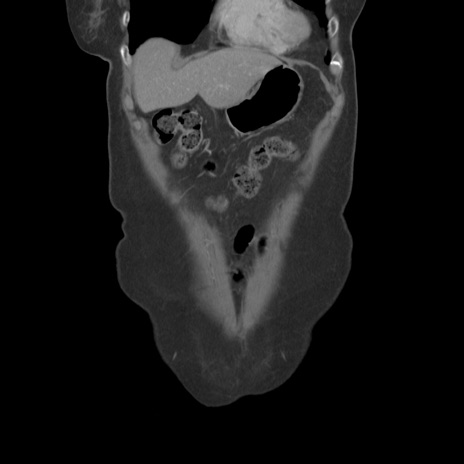

症例19(冠状断像)

【症例】80歳代女性

【主訴】下腹部痛

【現病歴】約8時間前より下腹部痛の出現あり、救急外来受診。

【既往歴】両側付属器切除

【身体所見】意識清明、下腹部正中に手術痕あり、その部位に一致して圧痛と反跳痛あり。腸蠕動音は亢進。

【データ】WBC 9300、CRP 0.15

横断像